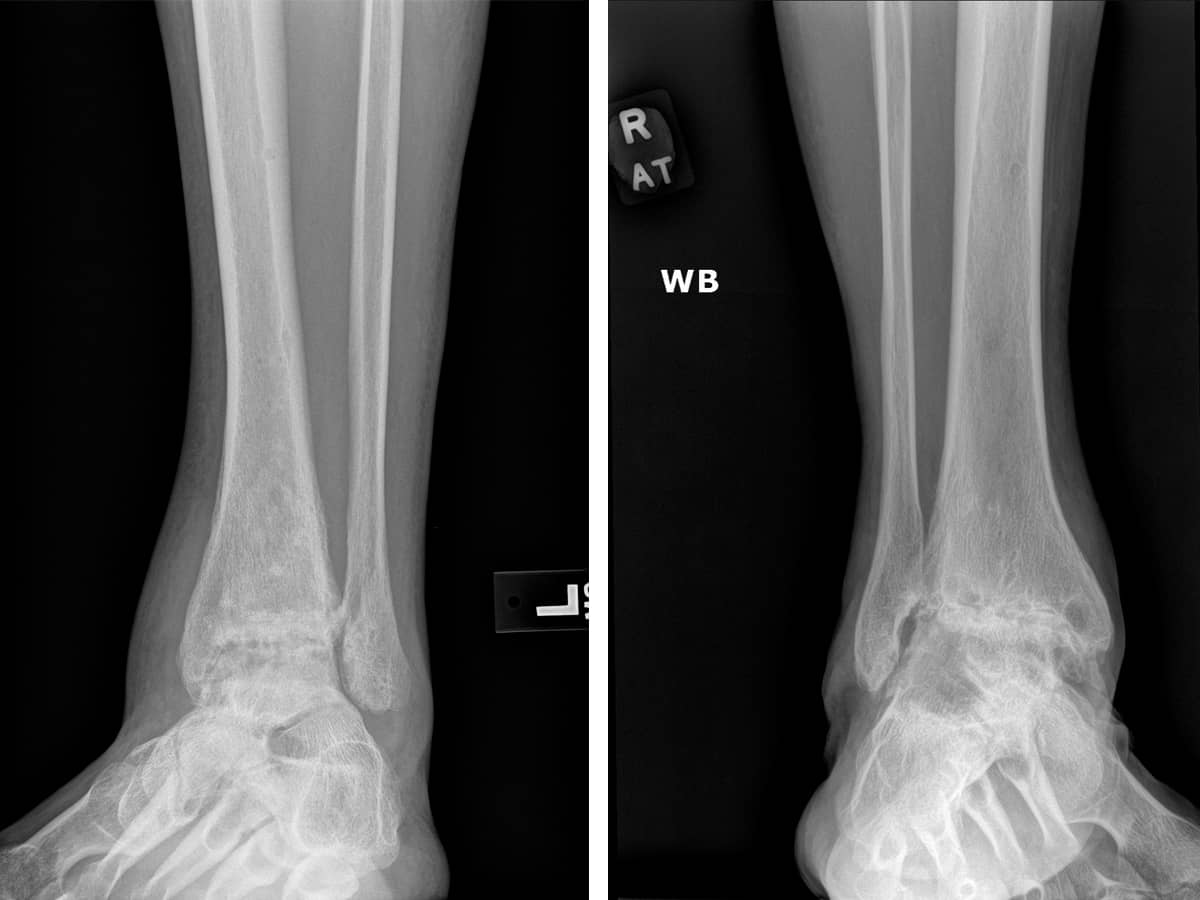

The relatively small ankle joint, compared to the knee or hip, handles the entire body weight of 2-3 million steps per year and doesn’t degrade. Only after an injury do the signs of arthritis, cartilage wear, pain, and inflammation appear. The difference in the cartilage within this joint gives surgeons novel opportunities to repair it when arthritis sets in.

Arthritis sets in if the ankle is not stable or if after fracture the reduction of the bones does not lead to perfectly smooth surfaces. Ankle cartilage repair procedures have improved. Our bias is to use an articular cartilage paste graft technique, but other forms of plugs and matrices have their proponents as well. Leaving cartilage injuries alone in the ankle leads to worse arthritis over time.

Severe arthritis of the ankle used to only be treated with either fusion or ankle replacement. Fusion can lead to a pain-free ankle but, over time, leads to wearing out of the joints below the fusion. Ankle replacements have improved from a dismal beginning to being useful for low-demand patients.

Something unique about the biology and the cartilage in the ankle has permitted us to trial a novel approach. Surprisingly, in our hands, a complete debridement of a severely arthritic joint with cartilage grafting of the worst areas of contact has led to a return to sports in a selected group of patients all of whom were told to have an ankle fusion. This data is still being developed so this technique has yet to be widely used.